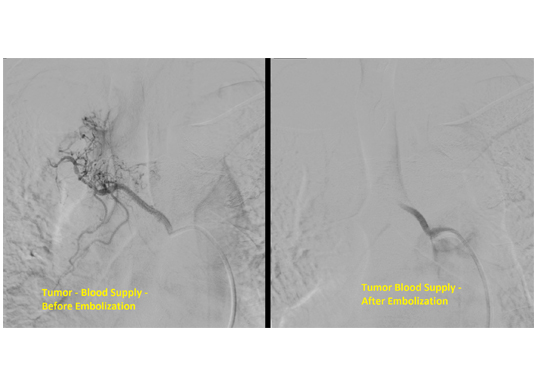

Spinal angiogram is done to assess the blood supply to the spinal cord. Below is a case of tumor with increased blood supply from a spinal artery. As the surgical removal is associated with increased blood loss, the blood supply was blocked of endovascularly.